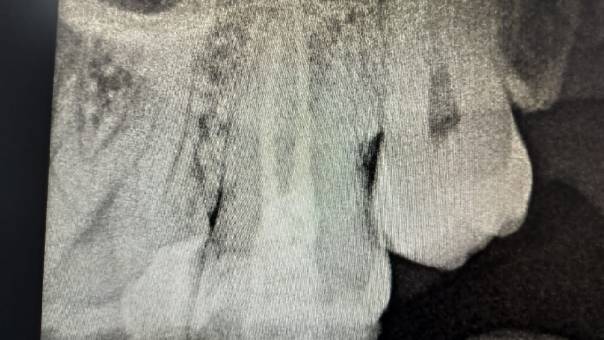

After Obturation

Clinical Outcome:

The procedure was done comfortably and successfully

on the patient, and recovery was smooth. At

follow-up visits, he reported complete relief from

pain, and healing was progressing as expected.